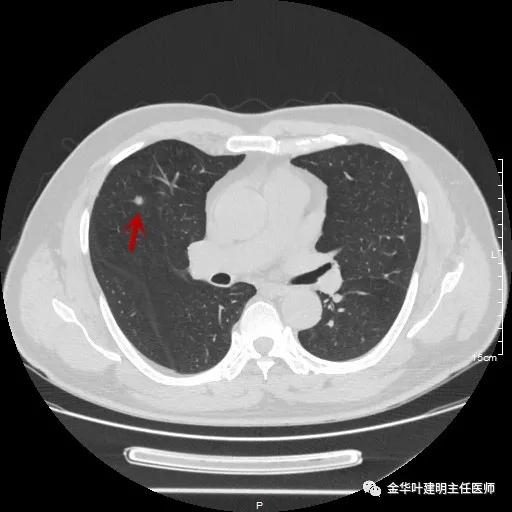

同样的地方,说明是同一病灶,但较1年前明显增大变圆,现在是圆形结节了,大小约在6-7毫米许,同样无明显磨玻璃成份,也无其他恶性征象,看着像肺内淋巴结或胶原增生结节或肉芽肿性结节。

其实分开看两年的片子都考虑是良性的,但问题是病灶进展增大了!该如何是好?另外内科接下来需行大剂量激素治疗,若为结核、若为真菌、若为肿瘤,大剂量激素会不会有影响?免疫抑制情况下,感染是不是要加重或扩散?真万一是肿瘤,是不是更可导致不良结果?此外,穿刺病灶太小太深,PET-CT有点小贵,而且这么小的结节,到底价值几何也难说。